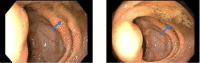

Ischemic colitis is thought to be an injury to the colon as a result of reduced blood flow. Certain infectious diseases such as the Epstein-Barr virus can aid in the reduction of blood flow. The insult can range from inflammation and superficial injury to full-thickness necrosis. The typical regions affected are the "watershed" areas of the colon: the splenic flexure, the rectosigmoid junction, and the right colon. Because patients can present with a wide spectrum of symptoms from vague abdominal discomfort to complete abdominal catastrophe, the diagnosis of ischemic colitis is sometimes challenging to make. Patients typically present with the acute onset of crampy abdominal pain and usually pass blood mixed with stool within 24 hours. Endoscopically, ischemia is suspected in the presence of bluish hemorrhagic nodules from submucosal bleeding, cyanotic or necrotic mucosa with bleeding ulcerations, or a segmental distribution with an abrupt transition point between injured and normal mucosa. We present a case of an 80-year-old male with a history of hypertension, hyperlipidemia, and basal cell carcinoma of the scalp diagnosed with ischemic colitis associated with positive Epstein-Barr virus B cell lymphoma.